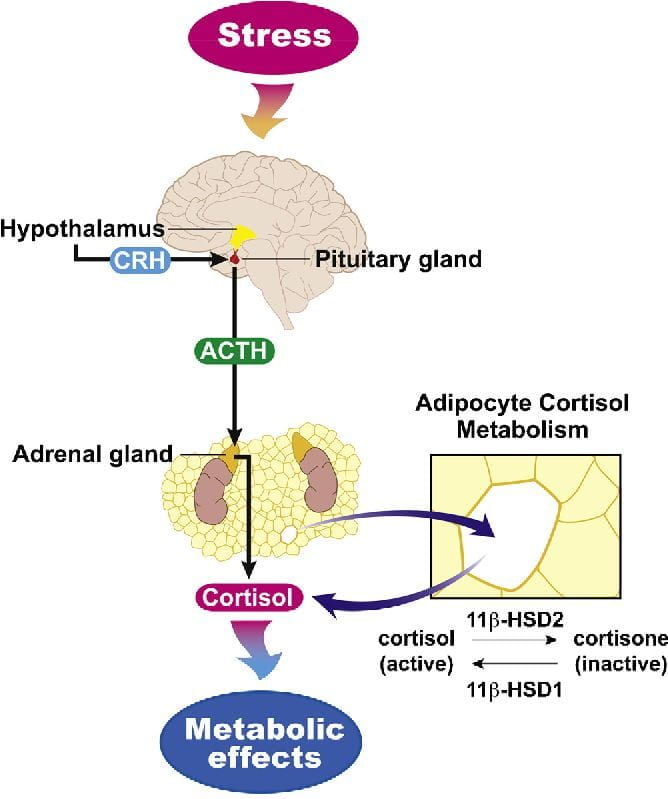

Hypothalamic-pituitary-adrenal axis Dysregulation and Cortisol Activity in Obesity: A Systematic Review. Read more.